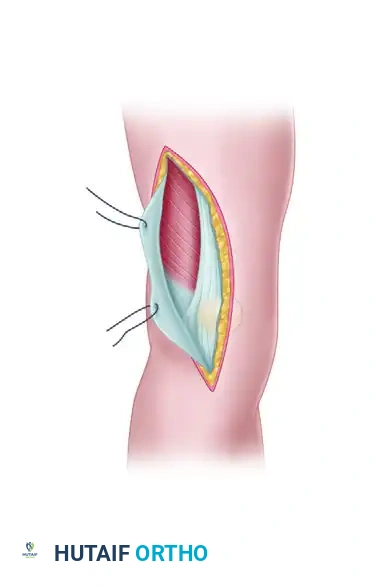

- Incision and Fascial Dissection: A midline or slightly lateral anterior longitudinal incision is made. The fascia overlying the quadriceps is incised longitudinally and lifted laterally off the underlying muscle belly.

FIGURE 54-74 A: Swashbuckler technique. The fascia overlying the quadriceps is incised longitudinally and lifted laterally off the underlying muscle.

- Arthrotomy: Farther laterally, the fascia over the quadriceps becomes confluent with the iliotibial band. A lateral parapatellar arthrotomy is performed. Proximally, the arthrotomy incision is carefully developed between the vastus lateralis muscle and the lateral retinaculum of the knee.

FIGURE 54-74 B: Swashbuckler technique. The lateral parapatellar arthrotomy is performed, separating the vastus lateralis from the lateral retinaculum.